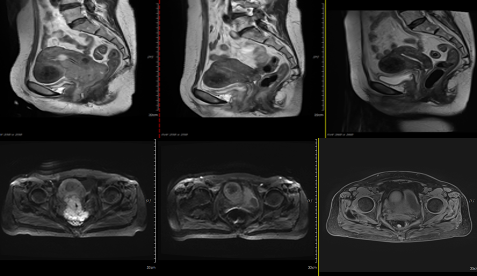

患者,女性,61岁,盆腔MRI提示宫颈占位,累及宫体、宫旁间质及阴道下1/3,考虑宫颈Ca,局部与膀胱后壁和直肠前壁界限欠清,肿瘤大小7x6.1cm,双侧髂血管周围多发小淋巴结,转移可能性大,临床诊断:宫颈低分化腺癌癌,FIGO分期:IVa期。

注:图A、B为放疗前MR,病变约大小7x6.1cm;图C、D为放疗后MR,病变大小1.7x1.2cm,图E、F为放疗后1月MR,提示宫颈粘膜曾祖,未见明显肿瘤性病变,双侧髂血管旁淋巴结较前显示不清,疗效评价为CR。